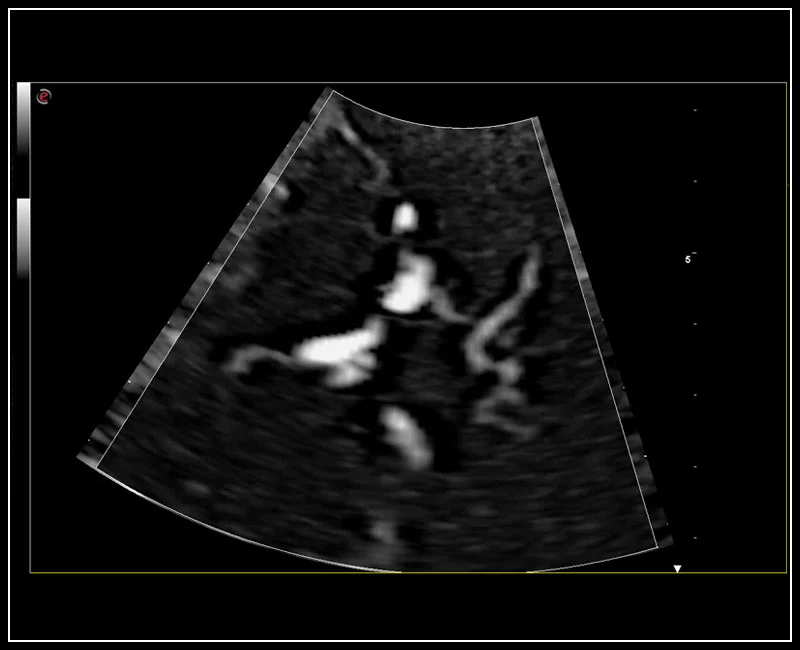

MyLab™E80 - microV - Kidney

MyLab™E80 - microV - Kidney

MyLab™9 Platform - Hemodynamics analysis using microV on kidney

MyLab™9 Platform - Hemodynamics analysis using microV on kidney